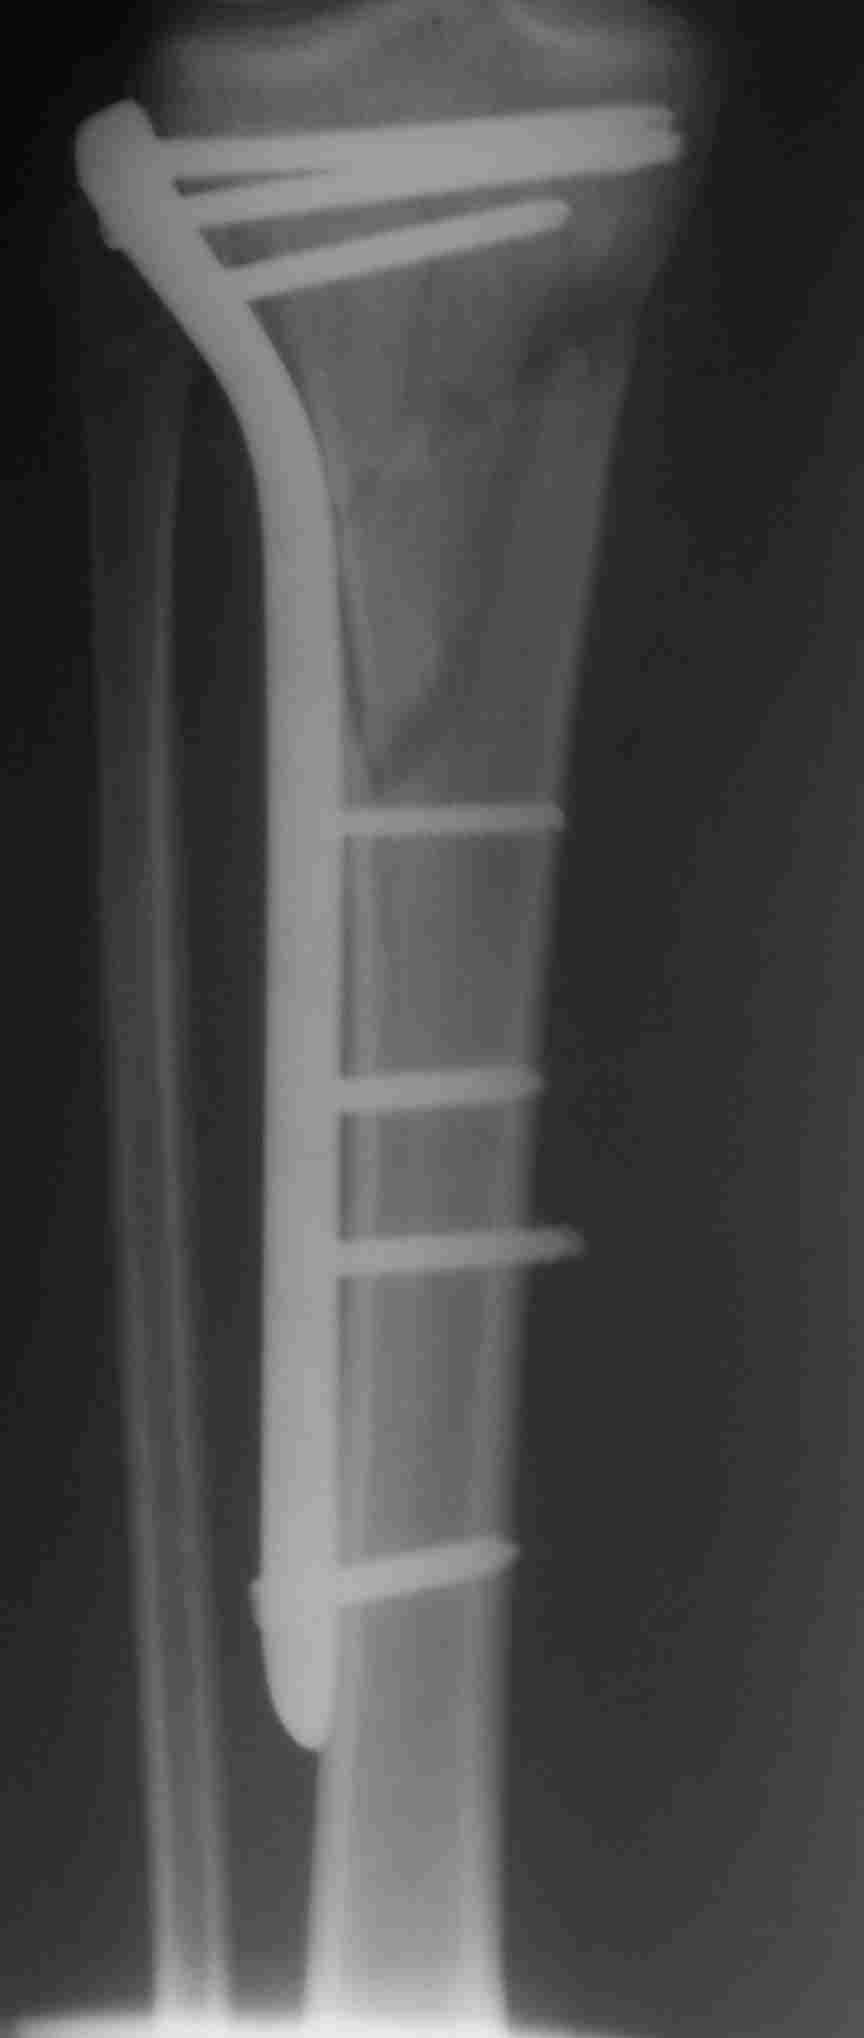

здравствуйте! создается впечатление о фиксации перелома голени в варусном положении

Согласен, на снимке “создается впечатление о фиксации перелома голени в варусном положении”, но на других отсутствует..

Похожий случай, вчера прооперировали. Непрямая репозиция, малоинвазивный остеосинтез без обнажения зоны перелома.